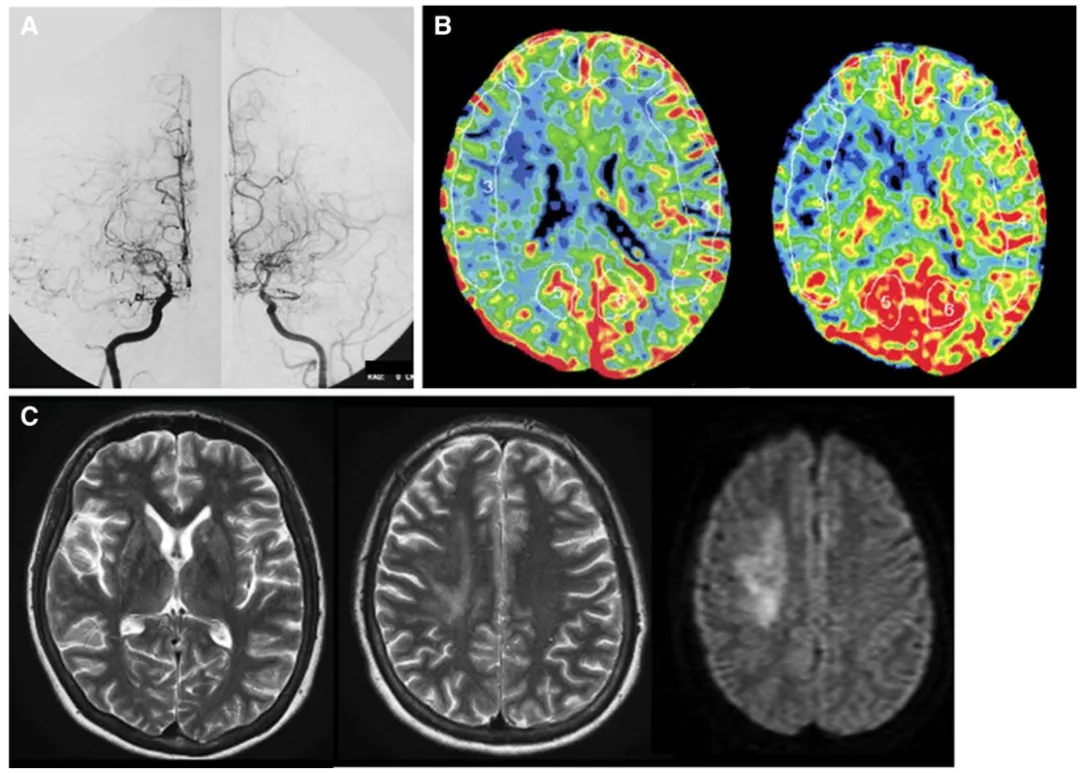

29岁的小薇清晨准备起床时,突然发觉左侧上肢与下肢出现沉重无力感,完全无法自主活动。前一晚尚是职场干练白领的她,此刻连翻身动作都异常困难。家人紧急送医后,经系列检查,两个陌生的医学诊断明确:她同时罹患烟雾病与格雷夫斯病。

进一步的甲状腺功能检测揭示了关键问题:她的游离甲状腺素(fT4)、游离三碘甲状腺原氨酸(fT3)水平远超正常范围,促甲状腺激素受体抗体(TRAb)亦显著升高,处于严重的甲状腺毒症状态。这让本就因脑梗导致偏瘫的小薇,病情变得更加凶险。

医生面临着一道棘手的诊疗难题。从烟雾病的治疗角度出发,小薇的脑血管狭窄闭塞已引发脑梗死,急需通过颞浅动脉-大脑中动脉(STA-MCA)旁路手术进行血运重建,以改善脑部供血。否则可能出现新发脑梗,加重神经功能损伤。

经过60天的精准调控,小薇的甲状腺毒症实现临床缓解,fT3、fT4指标降至接近正常范围。在确诊发病后的第195天,小薇的甲状腺功能达到了手术安全标准,医生判定实施血运重建手术的时机终于到来。

手术当日,医生团队为小薇实施了右侧STA-MCA旁路手术。术中采用微多普勒超声和吲哚菁绿荧光血管造影技术,实时验证旁路血管的通畅性,确保脑部血运重建的效果。整个手术过程顺利完成。